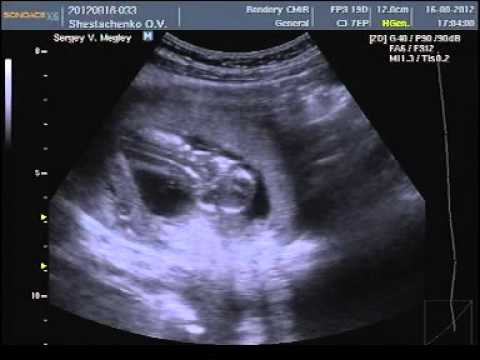

Разумеется, точно пересчитать малышей в вашем животе сможет только врач во время УЗИ (сделать его можно уже на 4–5-й неделе беременности).

Благодаря современным методам диагностики, многоплодная беременность определяется еще на ранних сроках. Во-первых, врач может диагностировать двойню при обычном осмотре – обратив внимание на быстрое увеличение размера матки или услышав двойное сердцебиение. Опытный специалист может диагностировать двойню уже после 4 недель беременности. Во-вторых, двойня диагностируется при УЗИ-осмотре. Обычно это происходит после 12 недель. До этого будущая мать может только предполагать, что носит двойню – например, опираясь на семейную историю и частые случаи рождения близнецов в семье. Анализы крови достоверным способом определить двойню пока не являются.

Однако подтвердить, что у вас будет двойня, сможет только врач. Чаще всего это бывает заметно на УЗИ на 12-й неделе беременности. Если вы недавно узнали о том, что ждете близнецов, рекомендуем прочитать статью c советами при многоплодной беременности.

Иногда на шестой неделе беременности при трансвагинальном УЗИ можно зафиксировать биение сердца (или даже двух!). Тем не менее с какой-либо точностью о присутствии второго ребенка можно будет говорить только после УЗИ на 12-й неделе.

Для диагностики различных состояний, врачи часто используют УЗИ. Будущей маме предстоит регулярно проходить такое обследование. Именно этот метод позволит узнать, сколько малышей находится в матке. Стоит выяснить, когда можно определить двойню по УЗИ. Специалист может увидеть количество эмбрионов примерно в 5-6 недель. Но по разным причинам на маленьком сроке устанавливают, что в матке несколько плодов, не всегда. В ряде случаев врач точно диагностирует этот факт позже, например, во время скрининга в первом триместре.

- УЗИ на сроке 8-12 недель уже может показать присутствие двух или трех плодов. Но на таком сроке ошибка не исключается.

Самый точный способ подтвердить то, что у вас многоплодная беременность — узи диагностика. Этот метод позволяет на ранних сроках определить количество зародышей с точностью 99,3%.

С большой вероятностью двойня на УЗИ заметна после 5-ти недель, если совершается передвижение зародыша по направлению к матке и визуализируется два черных пятнышка. Обследование по УЗИ назначает личный гинеколог, если сможет заметить активный рост объемов матки. Чтобы узнать про наличие монозиготных плодов УЗД визуализирует их не ранее 12 месяцев. В данный промежуток времени у зародышей разделились пальчики на обеих руках, сформировывались пуповины и развивается 1, 2 плаценты. Исследование происходят систематически (ежемесячно) для своевременного распознавания присутствия/отсутствия патологий. Увидеть развитие двух плодов согласно диагностике на ранних сроках весьма затруднительно из-за специфик положения и особенностей УЗД техники (новейшие устройства имеют наиболее высокие возможности к точному осмотру).

Женщины с многоплодной беременностью должны быть под постоянным присмотром. Определить многоплодную беременность можно на УЗИ, также как при обычной беременности. На сроке в 5 недель на УЗИ можно увидеть, сколько малышей родится.

Многоплодная беременность на раннем сроке

Врач определяет двойню на УЗИ на 5 неделе. Провести исследование можно раньше, когда матка сильно увеличивается. При беременности двойней врачи назначают УЗИ один раз в месяц. Так им видно как развиваются малыши. На 5 неделе не удается определить пол или количество эмбрионов. Это может возникнуть из-за качества УЗИ.